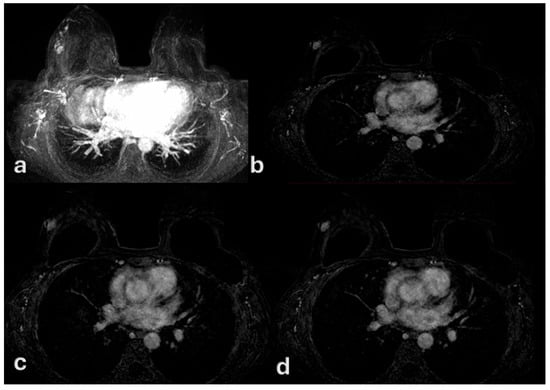

3. Results